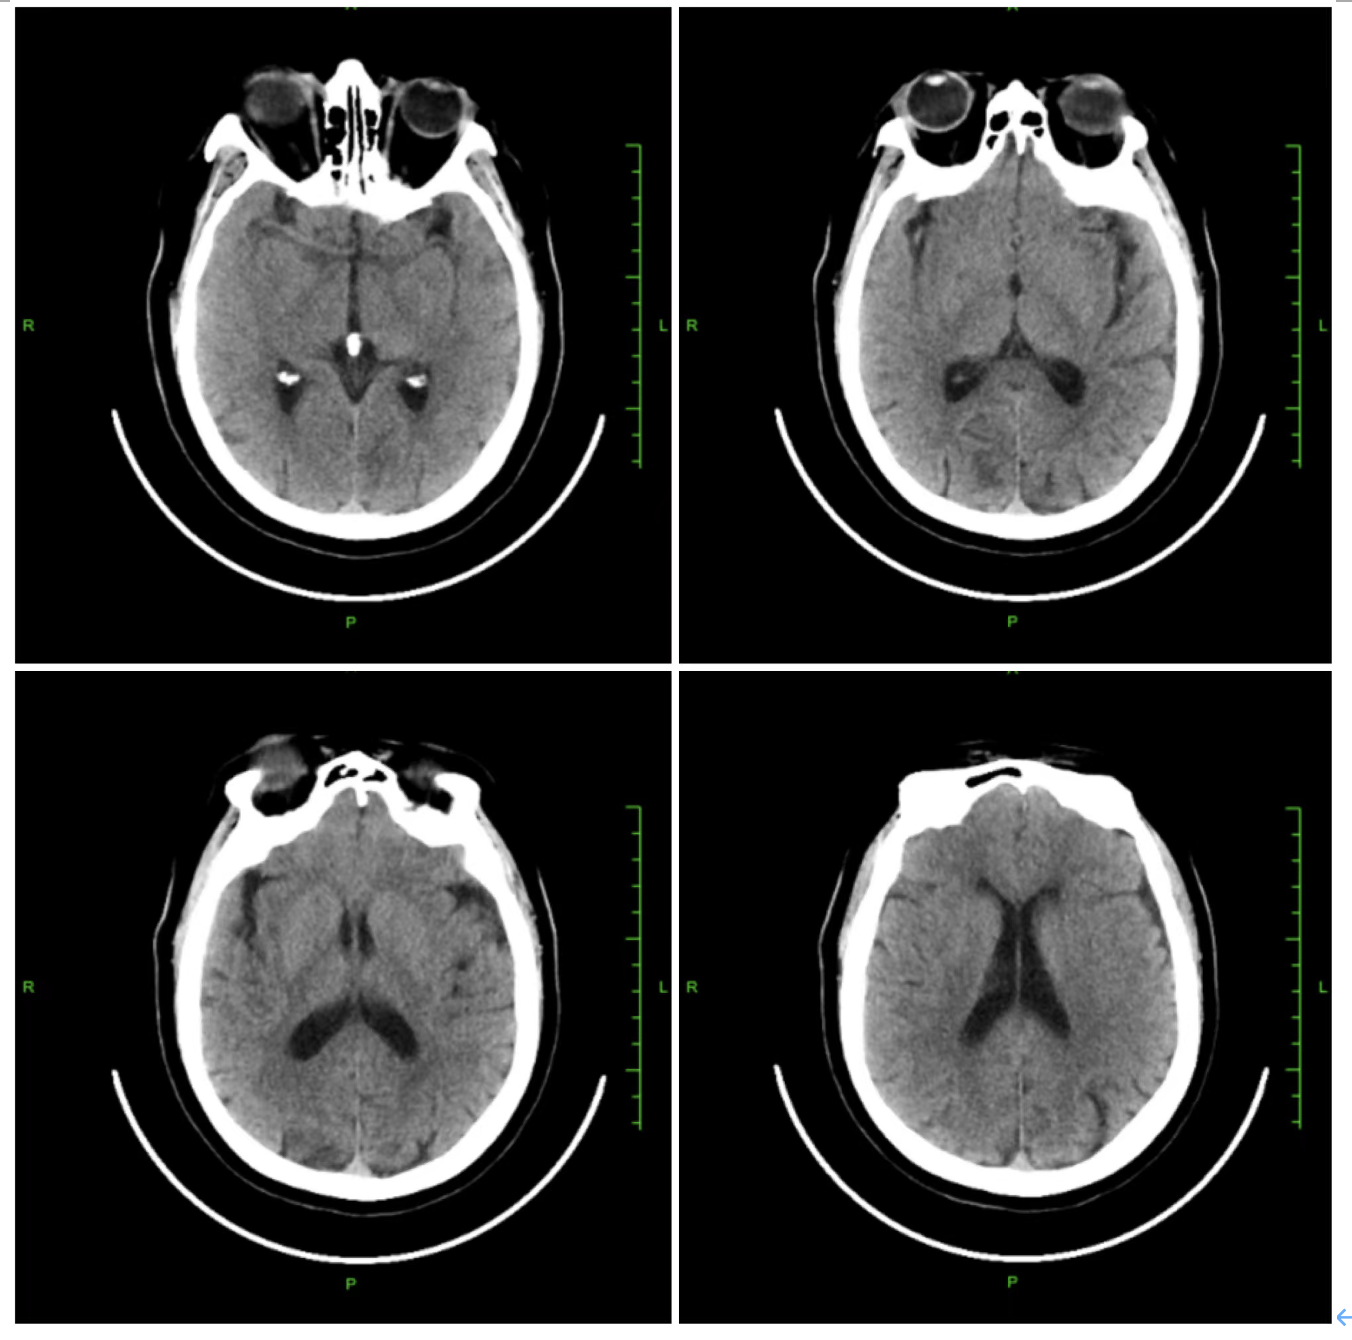

术前影像学检查结果:急诊头颅CT:可见右侧大脑中动脉高密度征,右侧半球未见明显出血及低密度影;头颅DWI:右侧颞叶大面积脑梗死。

7、术后情况:术后12小时,患者凝视消失,语言流畅,左侧肢体肌力恢复至3级,头颅CT复查:右侧颞叶无症状少量出血灶,散在低密度影。次日,左侧肢体肌力恢复至4级。